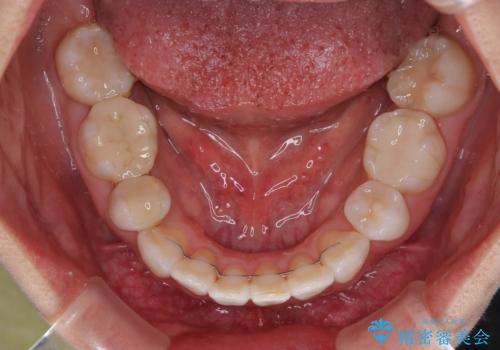

- 上下前歯の後戻りを気にして来院された患者様です。

インビザラインでの治療を希望されていて、デコボコの程度が中等度であり、安価なパッケージにて対応可能と判断されたため、インビザライン・モデレートを用いて矯正治療を行うこととしました。

インビザライン・モデレートは、製作できるアライナーの枚数に制限があるため、移動可能な量に限りがあるものの、インビザライン・ライトよりも枚数が多いため、幅広い症例に対応可能です。